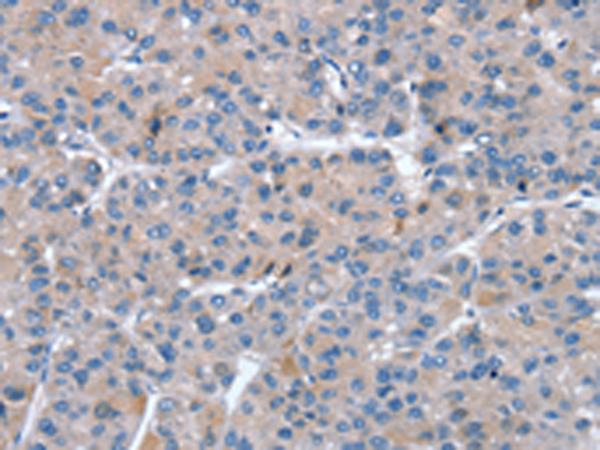

分类: 科研抗体货号: P08772别名: CTLN2; CITRIN; ARALAR2应用: WB,IHC反应种属: Human, Mouse